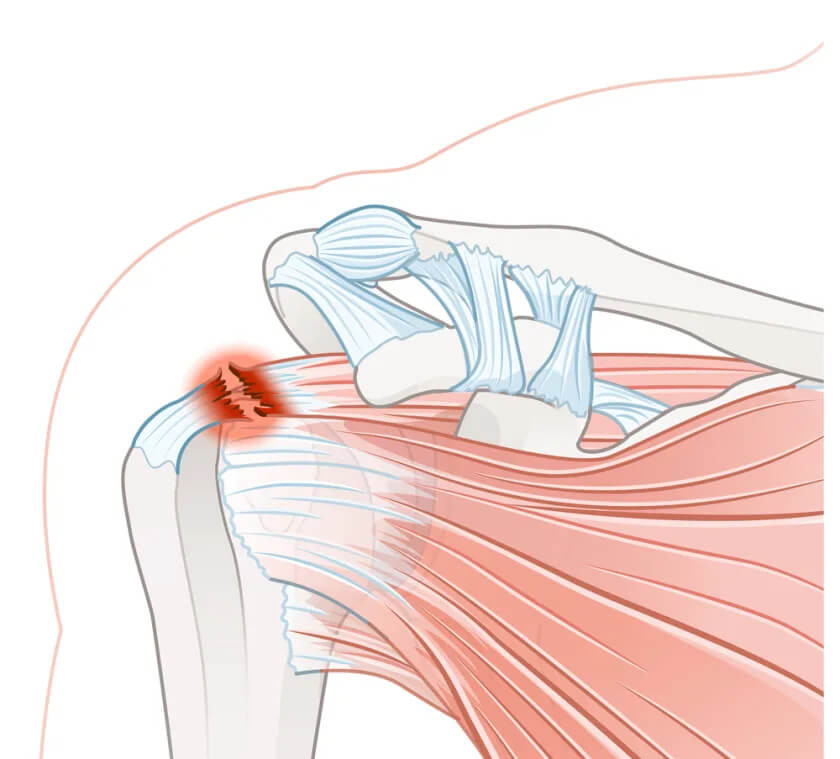

Повреждение вращательной манжеты плечевого сустава

Повреждение ротаторной манжеты плеча – одна из наиболее распространенных патологий плечевого сустава, которая сопровождается нарушением его функций, снижением стабильности, болевым синдромом. Вращательная, или ротаторная мышечная манжета – это передняя наружная часть капсулы плечевого сустава, она состоит из 4 мышц (надостной, подостной, подлопаточной и малой круглой). Их сухожилия крепятся к головке плечевой кости и за счет передачи мышечных сокращений обеспечивают движение руки в различных направлениях. Ротаторная манжета вместе с хрящевой суставной губой и связочным аппаратом играет важную роль в стабилизации плечевого сустава. Повреждение вращательной манжеты плеча – это нарушение целостности одной, нескольких или всех мышц, мышечных сухожилий, которые ее образуют, чрезмерное растягивание или разрыв их волокон.